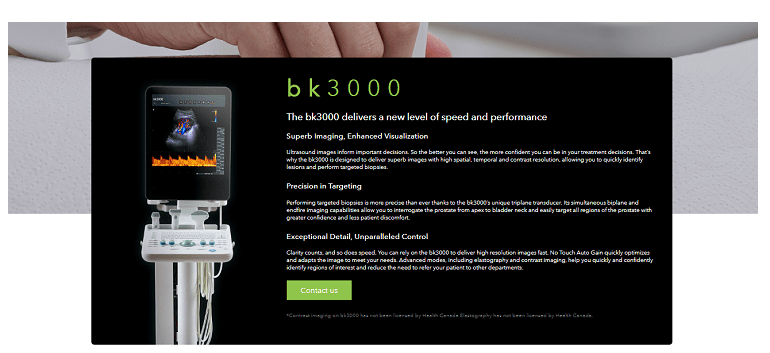

這種資源與類似資源之間的主要區別可以是產品卡。如果產品足夠簡單,例如出售藥品,消耗品,則卡的要求是標準的。但是,如果出售復雜的設備或昂貴的產品,則該卡的外觀和功能可能會完全不同。這是一個醫療網站例子。

該在線商店出售現代且昂貴的設備(超聲波機器)。目標受眾不需要號召性用語,不需要標準的潛在客戶生成按鈕或評論形式的信任塊。產品的詳細和專業描述在這里起著關鍵作用,它將表明其功能,功能和優勢。

同意,此產品卡與我們以前所見的產品根本不同。但同時,它完全可以滿足目標受眾的需求。用于聯系賣家的潛在客戶生成按鈕促成銷售,并允許您增加網站的轉化率。